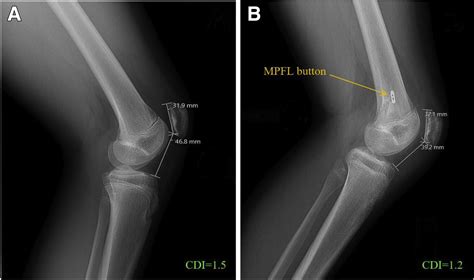

Medial Patellofemoral Ligament Reconstruction

This procedure is often performed in conjunction with other surgical techniques to address patellar instability. The medial patellofemoral ligament (MPFL) is reconstructed to provide additional support and stability to the patella, preventing it from dislocating or subluxing.